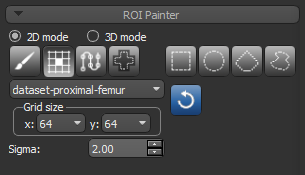

You can use the Smart Grid tool, as described below, or any other manual ROI Painter Tool to re-assign labeled voxels from one region of interest to another (see ROI Painter Tools).

- Click the Smart Grid

tool on the ROI Painter panel.

tool on the ROI Painter panel. - Select the dataset you are working with in the drop-down menu and then adjust the grid size, as required (see Working with the ROI Painter Tools in 2D Views).

- Select the region of the interest with the labeled voxels you need to re-assign in the Data Properties and Settings panel.

- Remove mislabeled voxels from the region of interest by holding down Left Shift (or your configured Remove by key) and then painting within the grid lines.

- Select the region of interest to which you want to add voxels.

- Add voxels to the required region of interest by holding down Left Ctrl (or your configured Add by key) and then painting within the grid lines.

- Scroll through the image slices and continue to refine the segmented regions, as required.